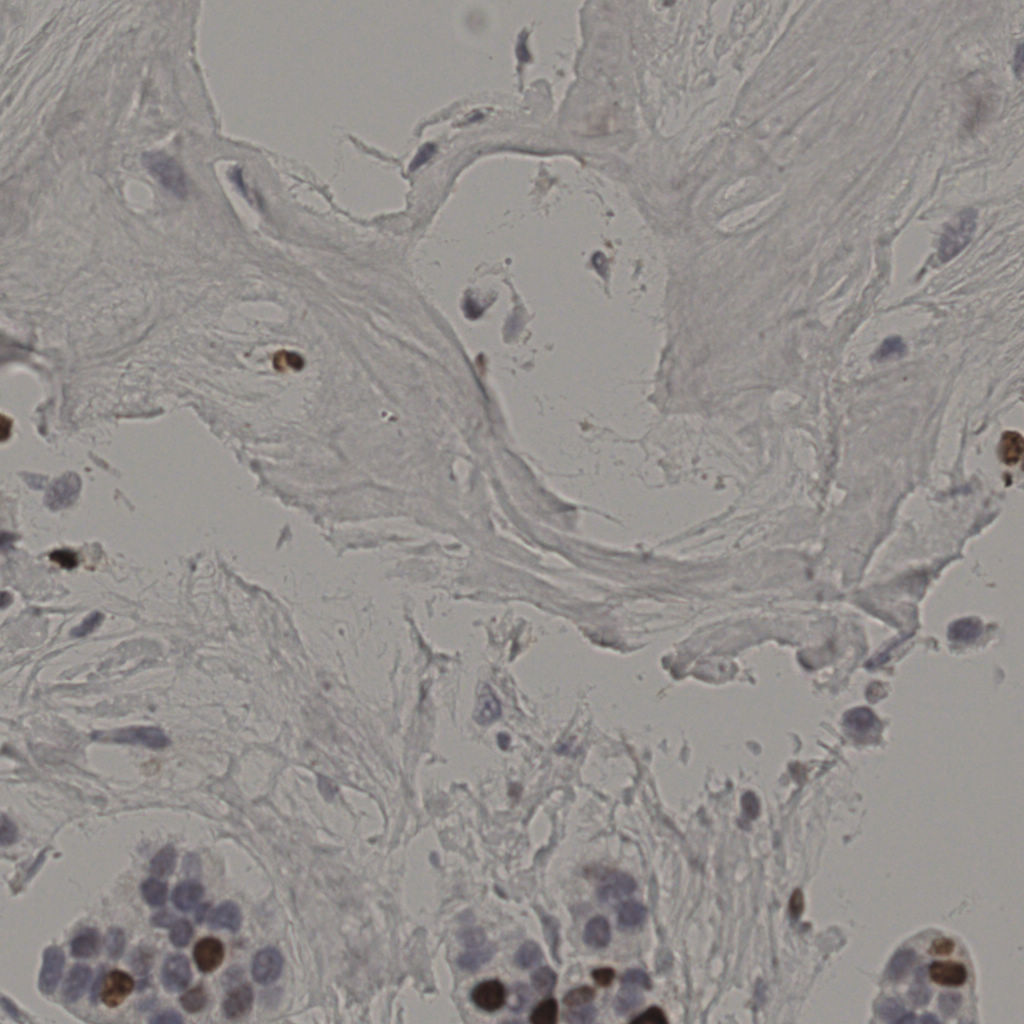

17.75%

Ki67 指数

阴 7986 阳 1723

20240285Ki-67.ndpi